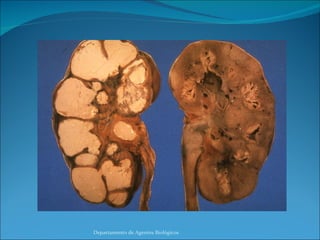

La Infección es lograda cuando el bacilo alcanza el alveolo pulmonar y posteriormente es fagocitada por los macrófagos del polvo, donde se replica intracelularmente.  El equilibrio entre la actividad bactericida del macrófago y la virulencia del bacilo es la que determina la efectividad de la fagocitosis. Formación de un granuloma produciendo lesión histica. Células multinucleadas de Langanhs – Necrosis Caseosa Diseminación – Fibrosis y Calcificación de lesiones pulmonares. Departamento de Agentes Biológicos

La Infección eslograda cuando el bacilo alcanza el alveolo pulmonar y posteriormente es fagocitada por los macrófagos del polvo, donde se replica intracelularmente. El equilibrio entre la actividad bactericida del macrófago y la virulencia del bacilo es la que determina la efectividad de la fagocitosis. Formación de un granuloma produciendo lesión histica. Células multinucleadas de Langanhs – Necrosis Caseosa Diseminación – Fibrosis y Calcificación de lesiones pulmonares. Departamento de Agentes Biológicos